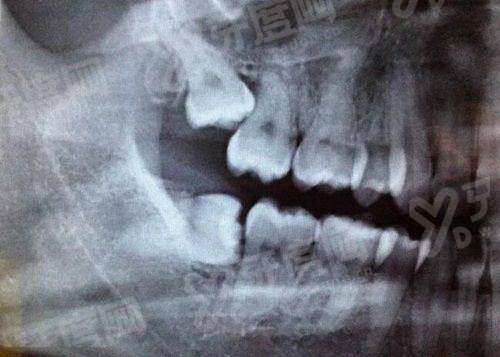

1、江苏拜博口腔医院采用 CBCT 三维影像扫描结合口内扫描技术,能在术前精细重建患者牙槽骨模型,让医生在电脑上提前模拟种植体植入的角度和深度。

2、通过制作个性化手术导板,医生在实操时能实现毫米级精细定位,有效避开重要的神经和血管,大幅降低了术中的出血量和术后的肿胀感。

3、这种技术特别适合牙槽骨条件复杂、多颗缺失或半口全口缺牙的患者,能让手术过程更加微创,修复周期也比传统盲种缩短了不少。